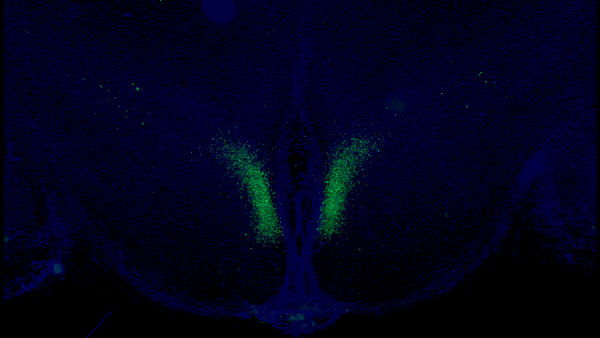

すると上の図の緑で示された、視床下部に存在する特定のニューロングループが白色脂肪組織に向けて信号を発していることが判明。

信号を受け取った脂肪組織はエネルギー源となる脂肪酸とeNAMPTと呼ばれる特殊な酵素が小さな小胞にパッケージされ放出されていることが明らかになりました。